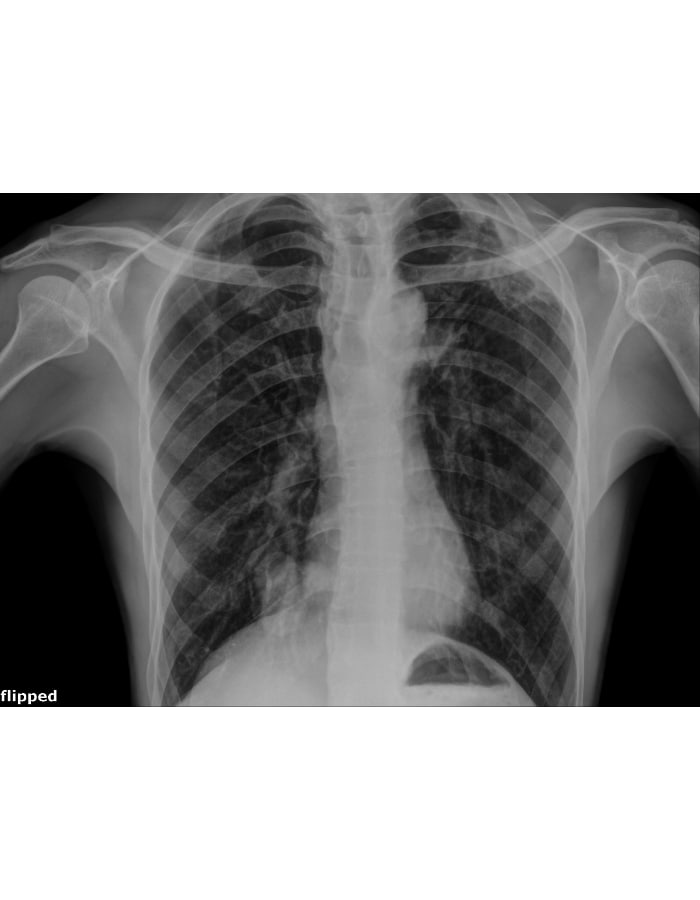

The image above, captured during our routine Active Case Finding in Addis Ababa, is more than just a scan—it is a life saved.

The individual in this image felt perfectly fine and had zero signs or symptoms. However, because of this technology, we found his TB early. He has already started his treatment and is now on the path to a full recovery.